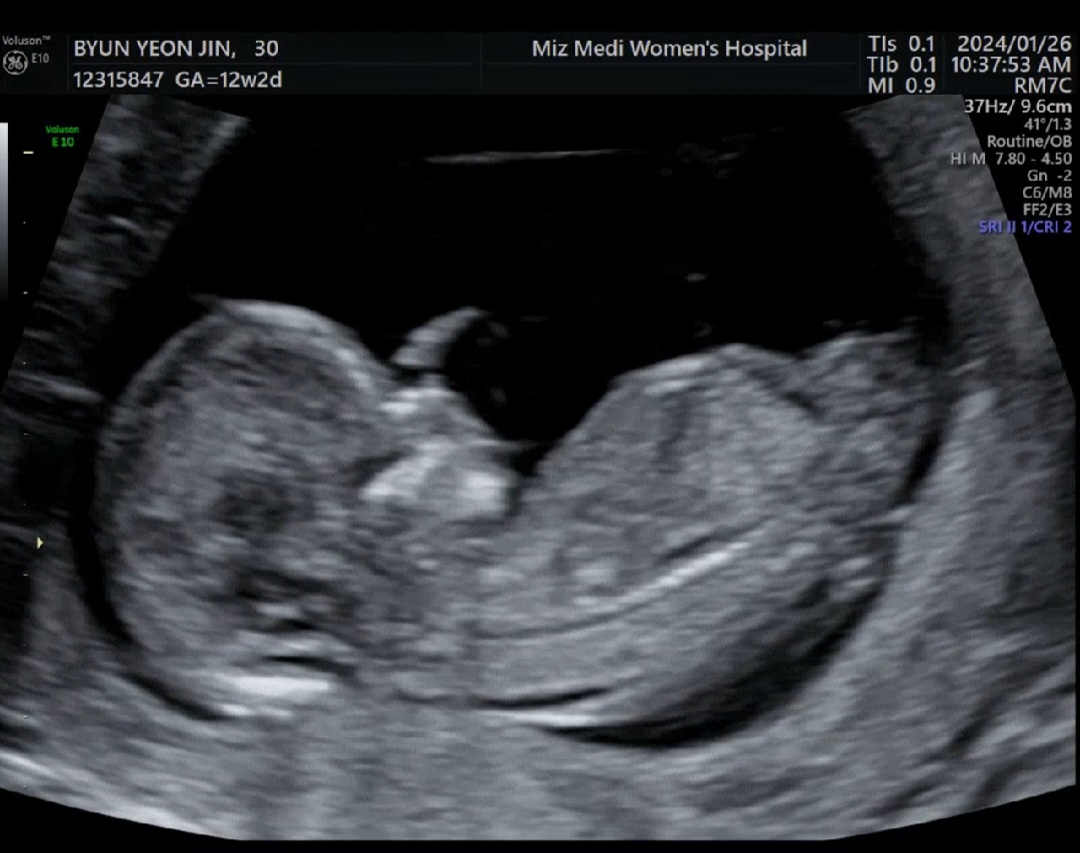

12주2일 각도법고수님 부탁드려요

아들일까요 딸일까요ㅎㅎ 그냥 너무 궁금하네요ㅎㅎㅎㅎ 각도법~~ 고수님들 알려주세용ㅎㅎ